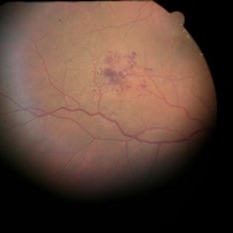

Retinal Cavernous Hemangioma

54 -year-old sent in with CME and Dx of BVO. She was 20/70. There are some exudates just nasal to the fovea at the edge of this photos, due to DME. There is a cluster of saccular aneurysms infero-temporally without any glial tissue overlying them.

Condition/keywords: cavernous hemangioma of the retina